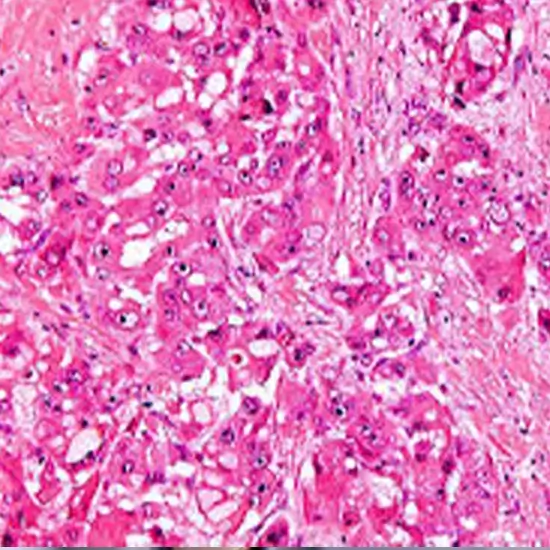

What is Cancer Marker Panel Test?

These screenings scan the blood, urine, or bodily tissues for tumour indicators, also known as cancer markers Screening tests are substances that are produced by malignant or normal cells in response to cancer in the body. Some tumour markers are exclusive to a certain type of cancer. Different types of malignancies contain other marker tests are typically not utilised to detect cancer or screen those at low risk of the disease because they can also appear in some non-cancerous disorders. The majority of the time, persons with a cancer diagnosis undergo these tests.